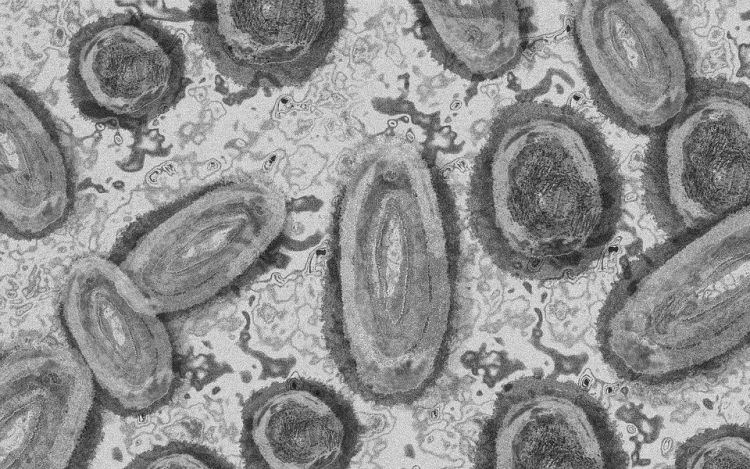

Belgiumban egy 3 év alatti gyermek fertőződött meg majomhimlővel - számolt be róla szerdán a Sudinfo hírportál.